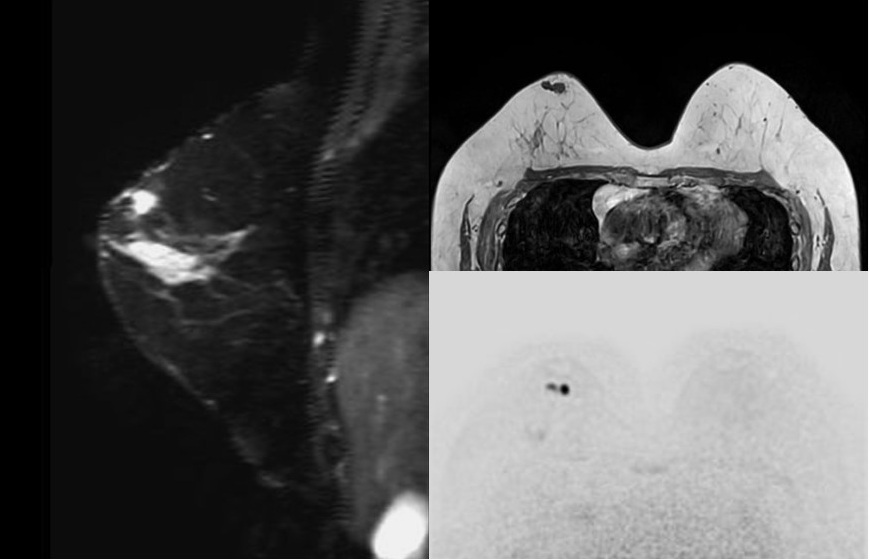

乳がんは日本人女性のがん罹患率第1位です。毎年9人に1人もの女性が乳がんに罹り、今もその患者数が増え続けています。しかし早期に発見して適切な治療を受ければ、高い確率で完全に治すことができます。乳腺MRI検査では、乳房専用の機器をMRIの寝台に取り付けます。検査時にはうつ伏せになっていただき、乳房専用の機器に乳房を入れ検査します。マンモグラフィのように乳房をはさんで圧迫することはありません。また、乳腺の状態は月経周期によって変化します。月経周期5日~14日の間が診断に最適です。

※まつ毛エクステ:乳腺MRIの際にうつぶせの体勢になることで形が崩れる可能性もあるため、まつ毛エクステを外しての検査を推奨しています。

●乳腺ドック:乳腺MRI

●乳腺ドック+乳腺エコー:乳腺MRI+乳腺エコー

●乳腺ドック:30分程度

●乳腺ドック+乳腺エコー:60分程度

検査日から1週間後を目安に郵送いたします。

医師による検査結果を当日ご希望の場合は、検査後30分程度お待ちいただきます。(※乳腺ドックは、隔週木曜・第2・4土曜・日曜に限り当日画像説明が不可です。)